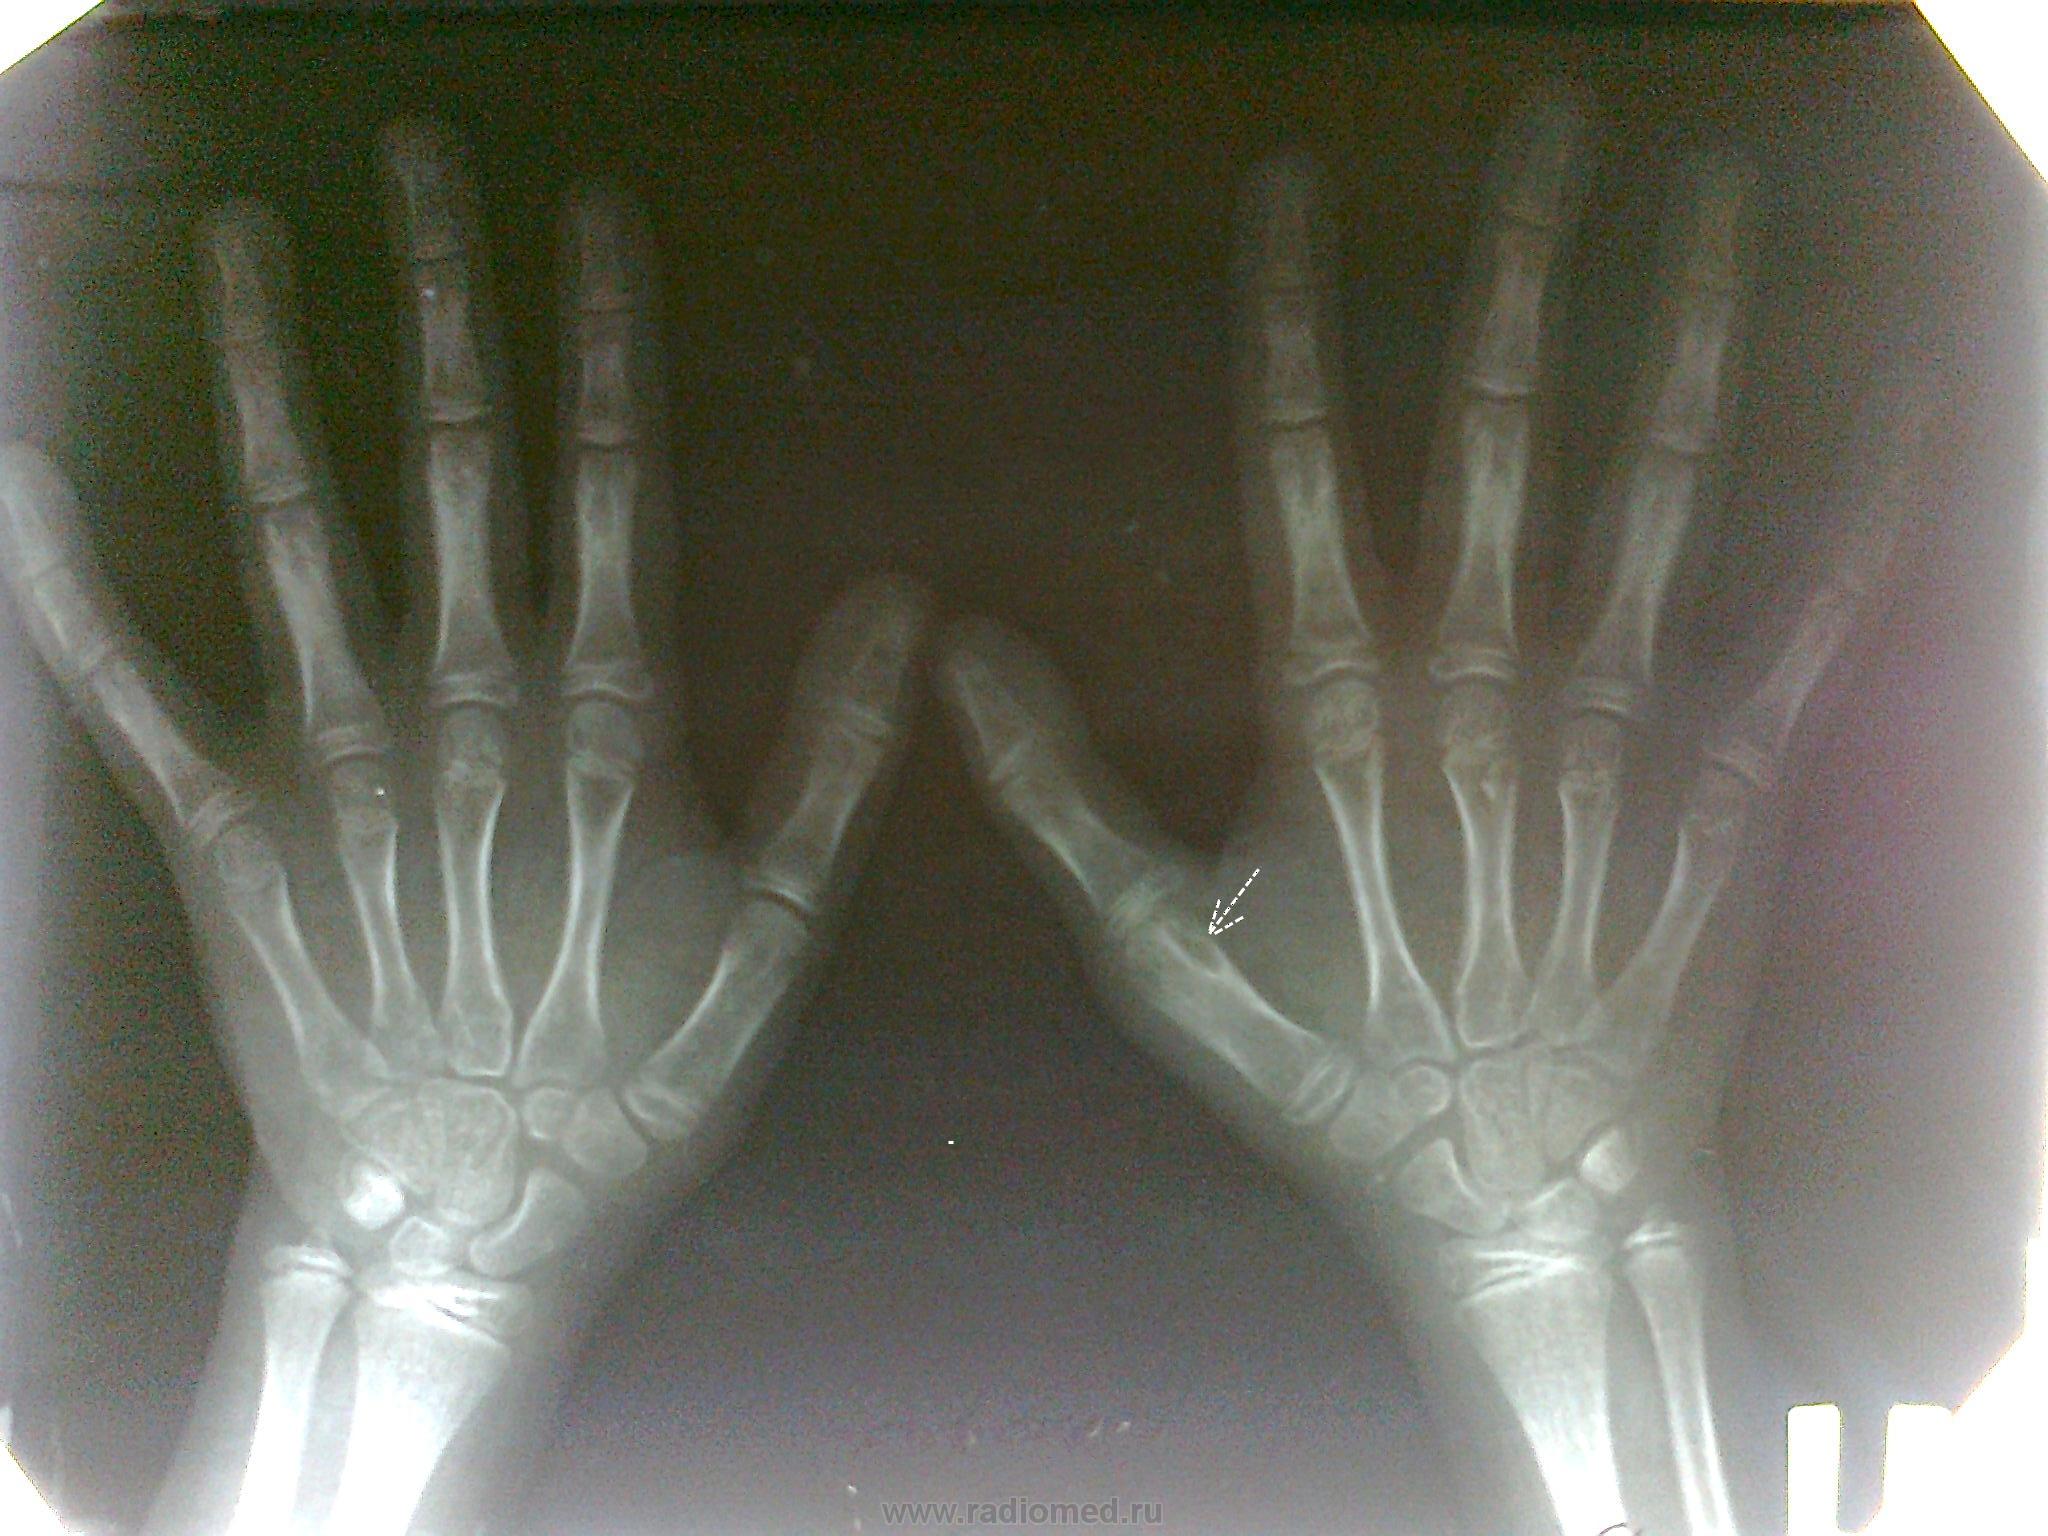

Не могу понять, у меня все открывается. Обратился ребенок, с  жалобами на боли в области 1 пальца и нарушение функции. Клинически определяется контрактура, сустав несколько увеличен, кожа не изменена. На рентгене подвывих в 1 плюсне-фаланговом суставе и очаг деструкции(?), который был расценен рентгенологом как киста. Отправлен на консультацию в стационар, поставлен предварительный диагноз остеомиелит, рекомендовано оперативное лечение. Время с момента травмы 2года, других жалоб кроме выше перечисленных нет.

Думаю, внутрикостный ганглий (юкстаартикулярная костная киста). http://www.radiomed.ru/publications/kss-vnutrikostnyi-ganglii    + застарелое повреждение связок.